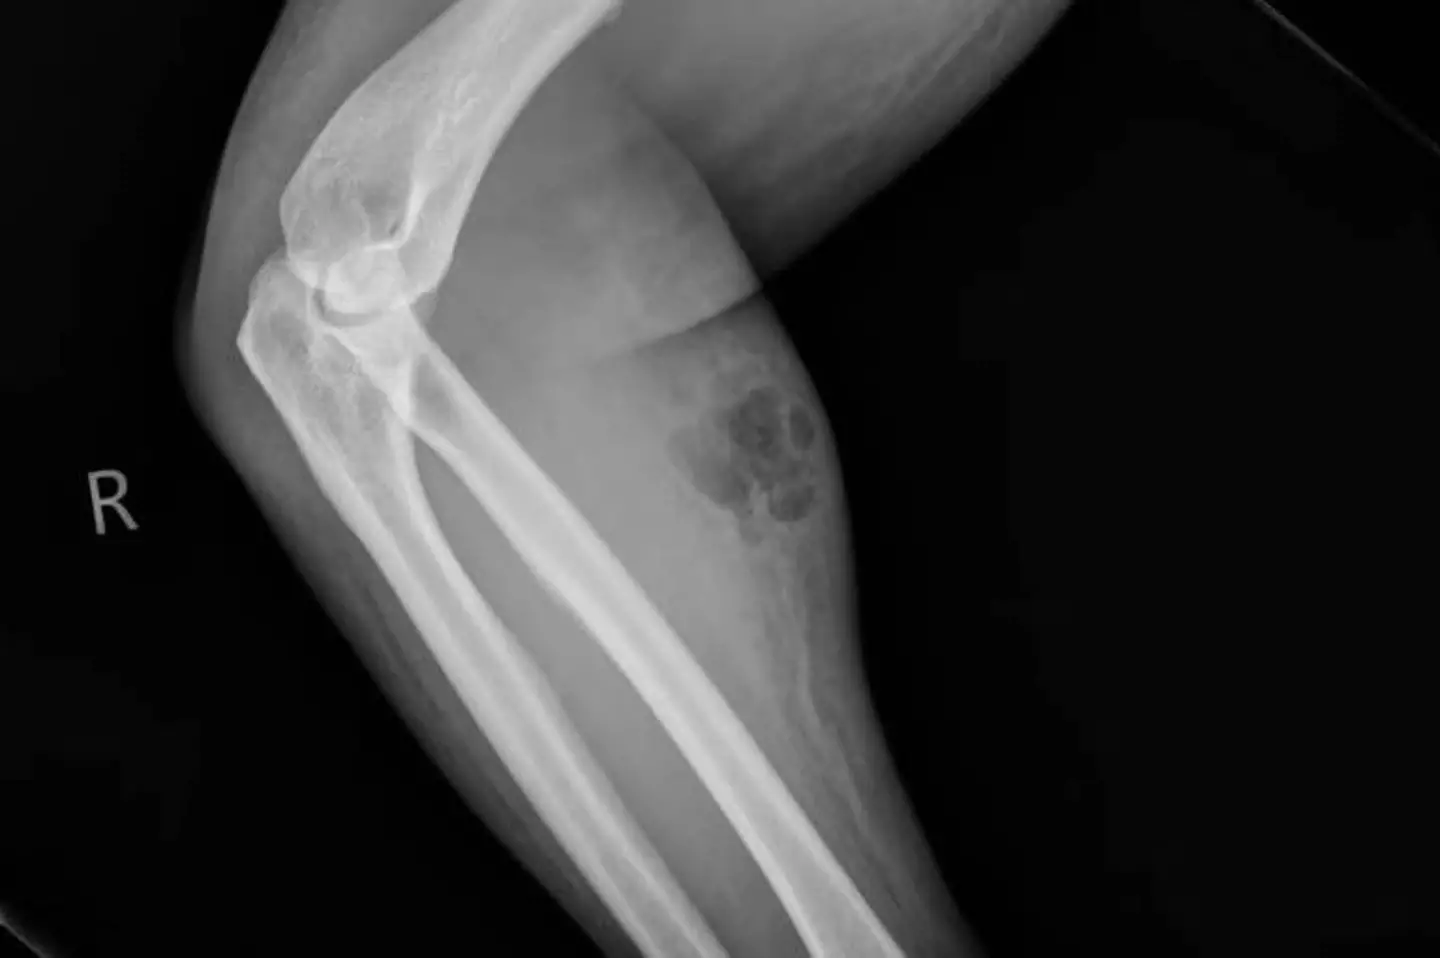

After undergoing an X-ray, he was told he was suffering from subcutaneous emphysema, which is a rare condition where gas or air is trapped under the skin.